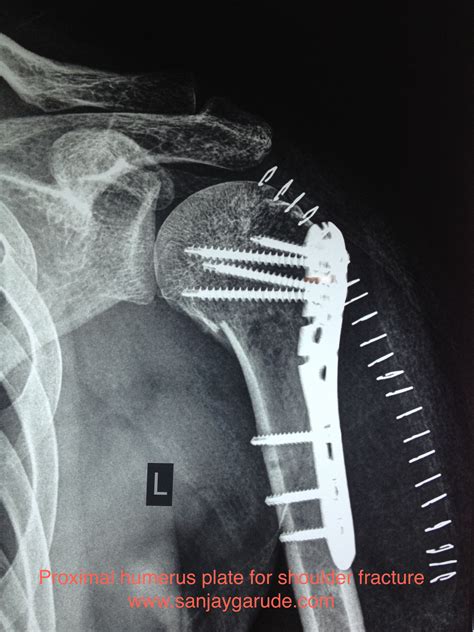

• Imaging Tests: X-rays are the primary imaging tool used to diagnose a fractured shoulder blade. They can show the location and extent of the fracture. In some cases, additional imaging tests such as CT scans or MRIs may be ordered to provide more detailed information.

• Open Reduction and Internal Fixation (ORIF): This procedure involves realigning the fractured bone and securing it with plates, screws, or rods to promote healing.